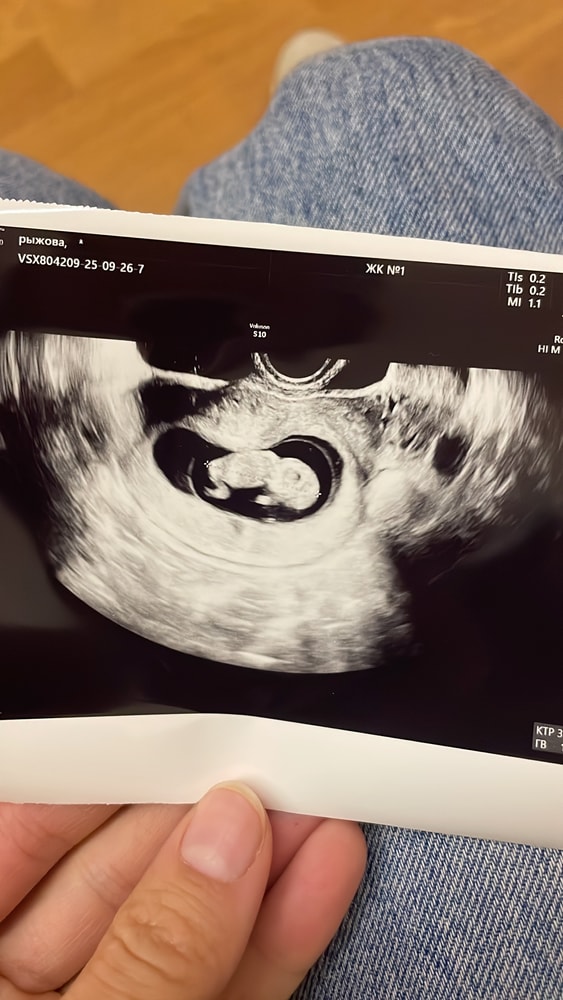

Всё о нашей беременностиСегодня 10 недель и 5 дней. Сходила на узи, после 2х недель выписки из больницы. Опять сказали тонус задней стенки((( в больнице при поступлении тоже он был, при выписке не было. Не понимаю что делать? Лежать в лежку? Я себя вроде берегу, работаю в 2 раза меньше, тренировки все закончила. Спрашивают тянет ли живот, а я не знаю. У меня так вздувается живот сильно. Что я не понимаю это матка или кишечник. Ну вроде иногда чуть чуть матка тянет. В поддержке Ипрожин 800 гр в день. Планирую снижать дозу, тк АЛТ высокий. Пришла идея магний может попить и посмотреть динамику? В общем девочки делитесь. Пс. С крохой и с остальным все хорошо (ттт)